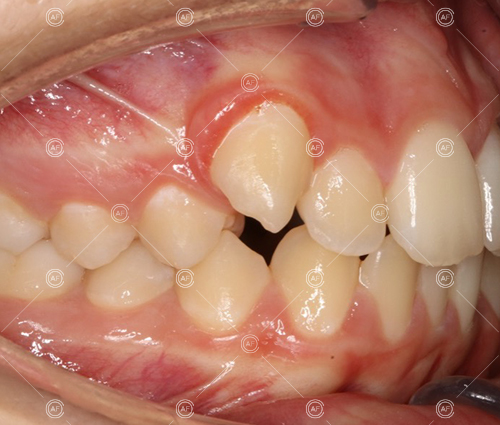

This patient (MH) began her active orthodontic treatment in October 2019 at almost 13 years old. She was unhappy with the appearance of her upper and lower teeth, and especially concerned about the unsightly nature of the high and buccally positioned upper left canine.

Buccal segments were essentially class 1 on the right hand side and a full unit class 2 on the left. This is due to buccal exclusion of the upper left 3 and mesial drift of the upper buccal segment.